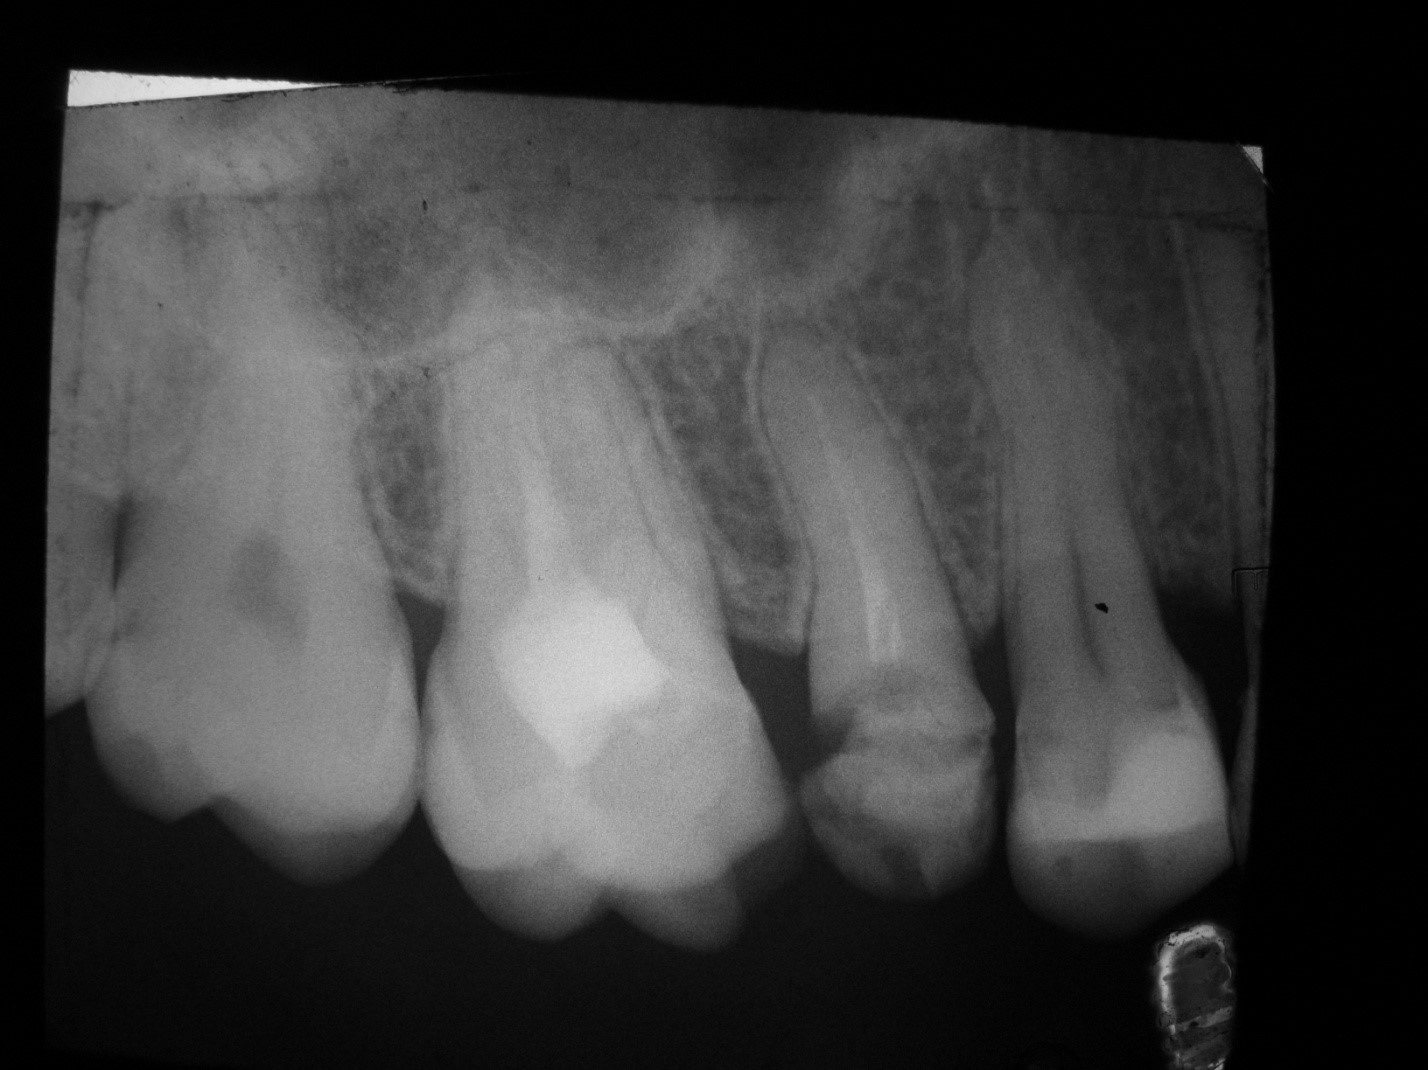

Рентгенологическое исследование назначается пациентам, у которых локализация кариозных поражений происходит на контактных поверхностях, под пломбами или под деснами. В таких случаях выявить проблему путем инструментального или визуального осмотра не представляется возможным. Использование рентгена позволяет с точностью до 80 % выявить наличие или отсутствие кариеса.

На фотографии показан рентгеновский снимок проблемного участка зубов. С помощью рентгена врач-стоматолог может увидеть состояние зуба и его корня. Без подобного исследования увидеть и понять что же именно тревожит пациента очень тяжело, и практически невозможно правильно диагностировать.